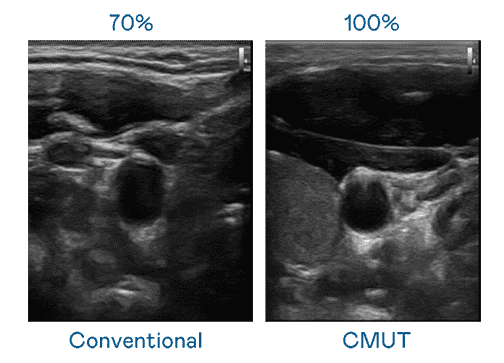

CMUT 技术是一种用电容式微机电元件来产生超音波讯号的技术。。与传统 PZT 压电式技术相比,,,CMUT 频宽增加 30%,,,,更宽频的超音波讯号让影像解析度大幅提升,,是实现高影像品质医疗超音波扫描、、促进精准医疗发展的关键技术。。。

大频宽带来超清晰影像

超音波影像的解析度高低,,,首先取决于探头能发出的讯号频宽。。28国际 CMUT 可提供高清晰的超音波讯号,,,,提供高频宽、、、、高灵敏度、、、影像纹理细节更高的超音波影像,,,协助医护人员缩短影像判读时间及利用精准的医疗影像进行诊断。。。。